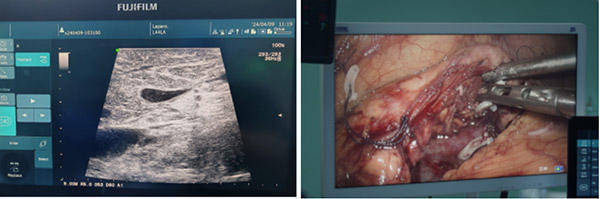

▲术中利用腹腔镜超声定位病灶(左),并在3D腹腔镜辅助下切除(右)

术中,徐进院长以娴熟的腔镜技术,精准找到病灶。虽然有大量的胰腺手术经验,但看到病灶的时候还是倒吸了一口凉气。病灶的确是非常棘手,它完全嵌入胰腺组织,没有边界,对门静脉压迫也非常明显。为了进一步掌握肿物情况,徐进院长采取了一个大胆、创新的手术方式,将胰腺颈体部充分游离并完全翻转,在超声科协助下利用腹腔镜超声技术,从胰腺正背侧反复辨认胰管与肿瘤关系,发现肿物横亘在肠系膜上静脉之上,距主胰管仅2毫米。透过3D腹腔镜的实时立体图像,徐进院长小心翼翼地分离胰腺与门静脉-肠系膜上静脉的间隙,像镌刻艺术品一样,一点点剥离瘤体直至完全暴露在视野中,精准地将肿瘤切除。切除后再次超声确认无胰管损伤。手术仅用时2小时,出血量不足10毫升。术后病理证实为良性肿瘤。